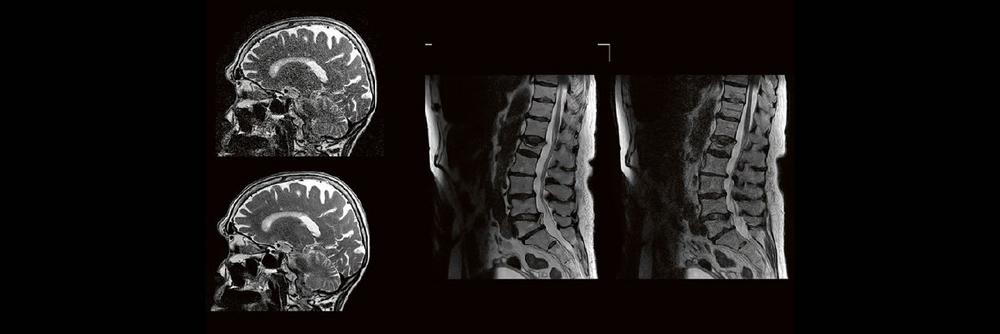

Blickdiagnosen im MRT für MTR (Webinar | Online)

Dorina Petersen In der täglichen Routine hat man wenig Zeit, sich lange mit den Bildern zu beschäftigen, die man anfertigt. Dennoch soll man auf bestimmte […]

DEEP-Learning-Rekonstruktion in der Neuroradiologie (Webinar | Online)

Professor Dr. med. Marc Brockmann WEITERENTWICKLUNGEN VON KOPF BIS FUSS BEIM VC Oberstarzt Dr. med. Stephan Waldeck DEEP-LEARNING-REKONSTRUKTION IN DER NEURORADIOLOGIE Die CT ist ein […]